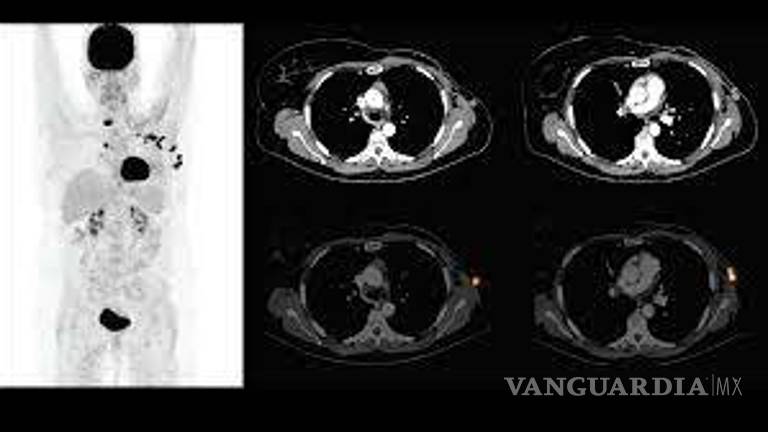

“Yo conozco mujeres que llevan seis meses sin recibir quimioterapias. Yo sé que las células mutan, y si pasa el tiempo son daños muy severos. No hay para un PET (tomografía por emisión de positrones). No hay para nada. Me han recetado estudios urgentes y no hay. Me han enviado hasta Monterrey a hacérmelo, y allá en Monterrey me dicen que no hay, que se descompuso la máquina. Fuera del área de oncología es excelente, pero fuera de ahí el trato es inhumano. Sí hay metátesis no voy a reparar en demandarlos”, dice la paciente.

De acuerdo con el testimonio, hay gente que tienen dos años esperando un PET y muchos pacientes se quedan callados. Luisa cuenta que una amiga murió hace algunos meses por falta de atención.

Después de enero del 2020, Idalia tenía que realizarse un PET para escanear su cuerpo y una vez más tuvo que viajar a la CDMX. La cita la pidió desde noviembre, pero le negaron el estudio que con un particular tiene un valor de 30 mil pesos.

Lo intentó en varias ocasiones y durante marzo, cuando inició la pandemia, le rechazaron la solicitud de estudio argumentando que estaban en enfrentando una epidemia. Ahora el estudio deberá hacérselo este septiembre, mes en que las autoridades del Hospital 20 de noviembre del ISSSTE en CDMX le dieron cita. Flor Idalia ahora tiene una sospecha en uno de sus pechos.

“Debí de haberme hecho el estudio más tarde en mayo. Es un escaneado que permite saber si hay metástasis o, en mi caso, una ligera sospecha que ahora tengo en mi pecho”, dice Idalia.